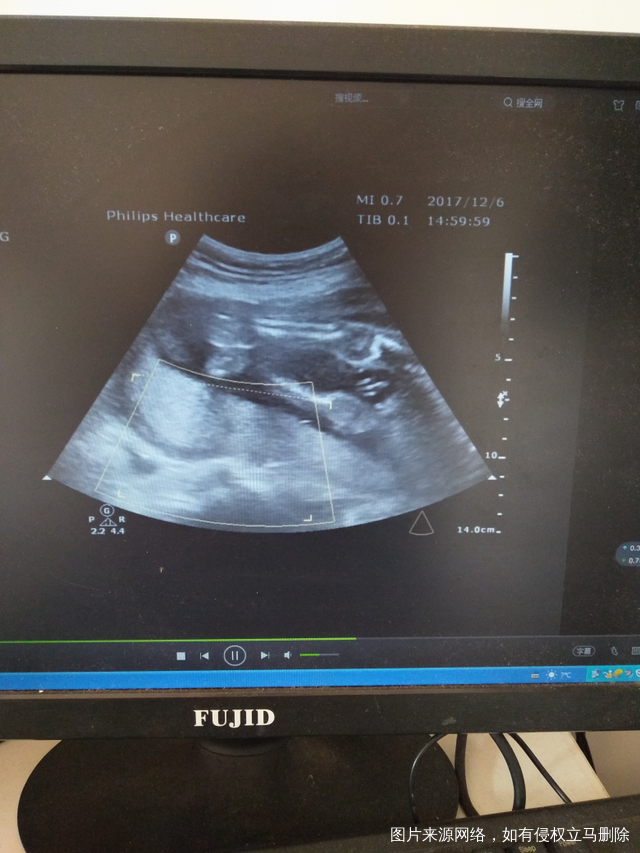

有宝宝的性器官图片 只是我还看不懂?有经验的宝妈可以帮我看一下

吗?